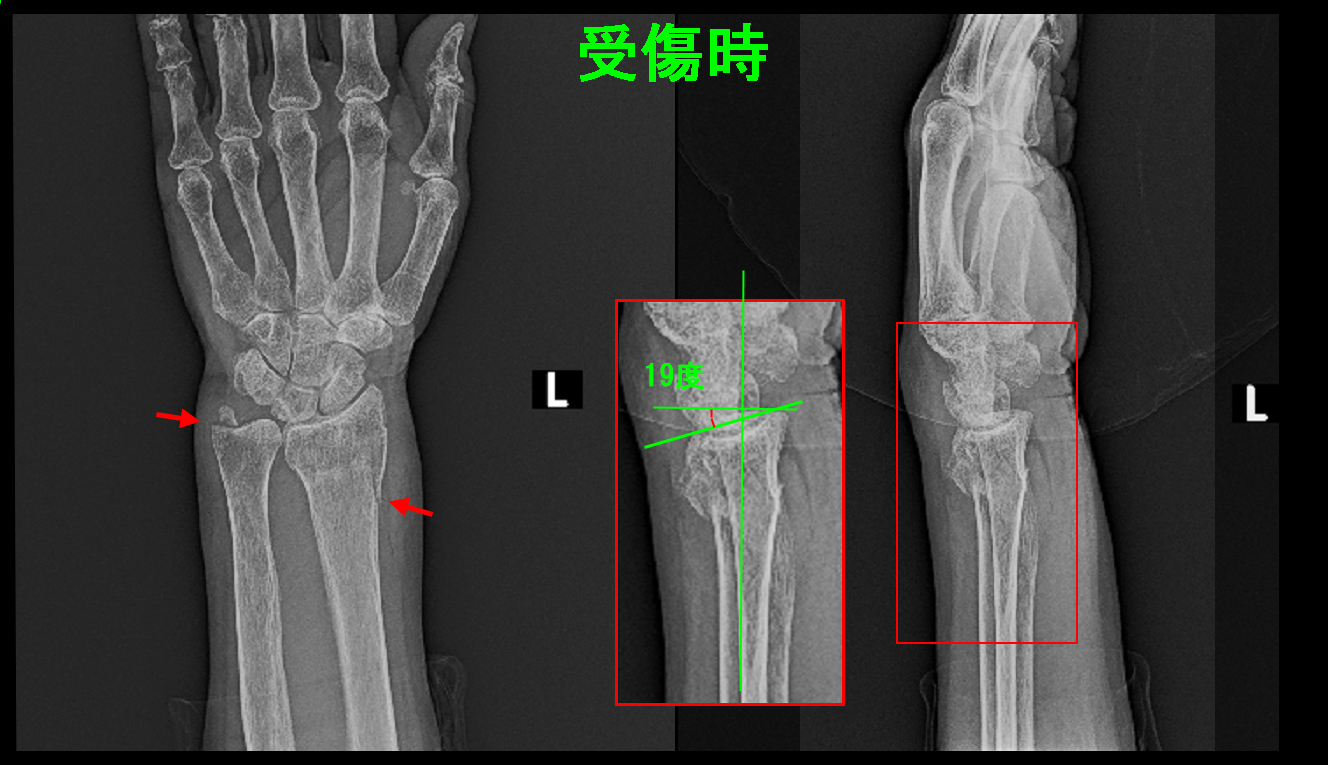

92才独居の女性の方です。Y年8月13日に庭で転倒し、左手をついて左手関節骨折(橈骨遠位端骨折)を受傷されました。同日、仲良しのお茶の先生に送迎されて当院を受診されました。

初診時Xp.jpg

骨折は手の甲側に19度傾斜しています。このままでは75才女性の患者さんのように手指のこわばりが続く可能性が高くなります。